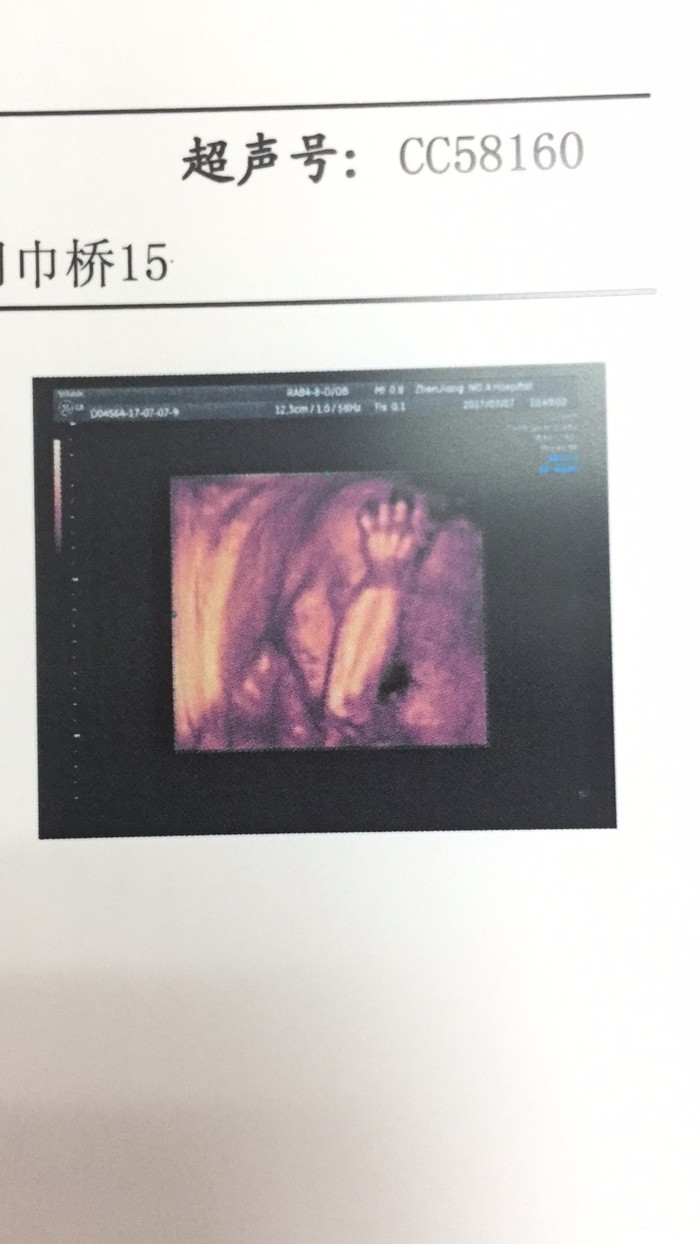

二宝的第一张丑照

感觉丑萌丑萌的~!!

害羞的二宝 不愿意露脸